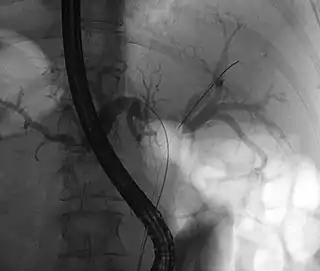

![]() Tumor de Klatskin durante ERCP. El paciente yace sobre su estómago de manera oblicua, por tanto el lado izquierdo de la imagen corresponde al lado izquierdo del paciente. A la izquierda y derecha del sistema biliar se coloca un cable que es necesario para las posteriores inserciones de stents para drenar la bilis. | ||